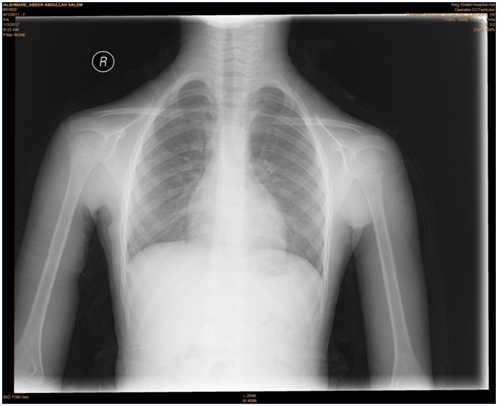

Figure 7 Chest and neck X-ray figure out and confirm that "there is no mediastinal extension of the mass".